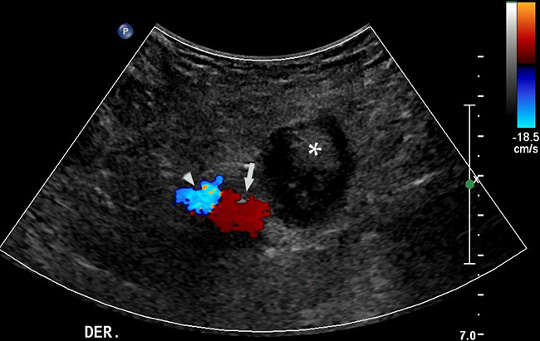

La hernia de Garengeot es una entidad rara, descrita por primera vez en 1731 por el cirujano francés Rene Jacques Croissant de Garengeot,1 quien reporta durante una exploración quirúrgica la presencia del apéndice cecal contenido dentro de una hernia femoral. Esas hernias ingresan al canal femoral ubicándose en el triángulo de Scarpa, destacándose por un mayor riesgo de complicación debido al pequeño tamaño de su anillo. Generalmente contienen intestino delgado y/o tejido adiposo visceral, siendo infrecuente la presencia del apéndice cecal (0,5-1% de los casos) y más infrecuente aún la concomitancia con apendicitis aguda (0,08-0,13% de los casos).2,3 Se presenta el caso de una mujer de 75 años con antecedentes de hipertensión arterial, dislipidemia, sarcoidosis, y derivación biliodigestiva reciente por estenosis de la vía biliar, en control y tratamiento. Consultó en el servicio de urgencia por cuadro de un día de aumento de volumen en región inguino-crural derecha asociado a dolor EVA 2/10, sin otro síntoma a la anamnesis dirigida. Cuando se realizó el examen físico, la paciente estaba afebril, destacando una masa sensible no reductible dela región crural derecha, sin otros hallazgos positivos que consignar. Los exámenes de laboratorio demostraron hematocrito 39,1%, Hb, 12,9 g/dL, leucocitos 9.600 u/mm3, neutrófilos 80%, plaquetas 242.000 u/mm3, VHS 14 mm/h. Por la sospecha clínica de una hernia crural atascada se realizó una ecografía abdominal e inguino-crural, en la cual se observó un saco herniario en relación a los vasos femorales derechos (Fig. 1), no reductible al paso del transductor, que presentaba contenido líquido y adiposo, ése último con aumento de su ecogenicidad debido a cambios inflamatorios. En su interior destacaba además la presencia de una estructura tubular de aproximadamente 10 mm de diámetro, no compresible, que no presentaba vascularización al modo Doppler color, y que se interpretó como el apéndice cecal con cambios inflamatorios (Fig. 2). Con ese diagnóstico, la paciente ingresó al pabellón quirúrgico sin realizarse otro estudio imagenológico. Durante la cirugía se identificó el saco herniario no reductible, que en su interior presentaba una estructura tubular correspondiente al apéndice cecal, el cual medía aproximadamente 11mm de diámetro, y que mostraba cambios de aspecto flegmonoso en su extremo distal. Se realizó un abordaje pre-peritoneal con ampliación del ligamento lacunar (Ligamento de Gimbernat), posteriormente reducción, apertura y resección del saco herniario. A continuación, se efectuó una apendicetomía con meso (Fig. 3) y cierre del peritoneo, para finalizar con hernioplastía primaria con dos puntos al anillo crural. La biopsia confirmó que la estructura extraída correspondía al apéndice vermiforme con hiperplasia de la mucosa, periapendicitis con hemorragia reciente y signos de organización. La paciente evolucionó en buenas condiciones, sin complicaciones postoperatorias.

Ecografía en eje transversal, se visualiza el saco herniario (asterisco) hacia caudal y medial de la vena femoral común (flecha) y arteria femoral común (punta de flecha). Se debe aclarar que en esta imagen existe una inversión de los colores habituales al modo Doppler color (vena en rojo y arteria en azul).